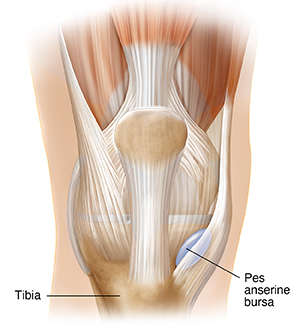

The pes anserine bursa is found on the inside of the knee joint. It lies between the shinbone (tibia) and 3 tendons that attach the hamstring muscles to the shinbone. Inflammation of this bursa is called pes anserine bursitis.